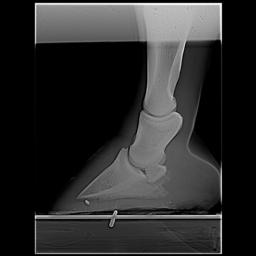

Posted on Thursday, Apr 5, 2007 - 1:11 pm: Dr O,I just read this article today after meeting with my vet and farrier yesterday regarding my horse's heel pain and I would like to get your input, if possible. I have had Remy for 6 years and have fought his low heel, long toe confirmation the whole time. In hindsight we did not do the right thing although we had the right idea. She said that if this had been managed properly for the past 6 years there would not be the damage there is now. I think the thing we missed was regular radiographs to see what was really going on. We just assumed that because he was not lame he was ok inside - the radiographs taken yesterday show that definitely was not the case. There is damage to the navicular, pedal osteitis, bone spurs and other things going on now. We have put him in 7 degree wedge pads with soft impression material. He walked off almost sound after the shoes were put on. I'm keeping a close eye on him because he can be sensitive to anything touching his sole as he has extremely thin soles. My vet said that it is important for sole growth that the frog had pressure - I had never heard that before. My vet said that it is possible that some healing can take place and he can return to regular work. She said that if the corrective shoeing doesn't work the next step would be injections - and she sounded pretty positive about the injections. We will continue to take regular xrays every 3 shoeings until we see the improvement we want. Does this sound like a good plan? I'm going to upload some radiographs that will give you an idea of what we are dealing with. I hope the thumbnails are large enough for you to view. I would greatly value any input you can give me. BTW I absolutely love this article! I'm going to print it and give it to my farrier. It's basically the same thing that he and my vet have said to me but it may have a couple extra insights. Thanks, Dawn Left front     Right front

Posted on Friday, Apr 6, 2007 - 6:36 am: Hello Dawn,I have moved your post into this new discussion. Using the radiographs as guides it would appear to me that the left could use around 7 degrees but the right a little less. This assumes the horse was standing square while radiographed. While radiographs are critical early in the assessment, because your feet do not appear to have any rotation of the coffin bone, you can assess proper balance without radiographs. This and how the foot responds to your work should be your guide to whether you have balanced these feet correctly. DrO |